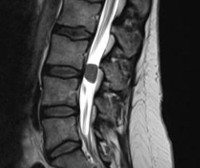

Это основной метод диагностики новообразований. Магнитно-резонансная томография позвоночника помогает определить размеры, точное местоположение, характер роста образования, степень компрессии позвоночника. При наличии противопоказаний для магнитно-резонансной томографии выполняется КТ-миелография.